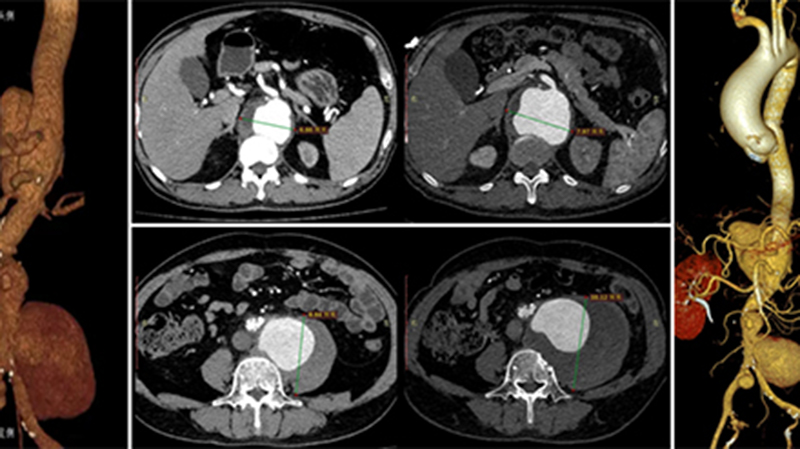

• 近期,伟德1949官方网站(山东省立医院)进行了2023年度技术创新奖和重大抢救奖评选。为让社会大众更深入、更精准地认识医院优秀科室,展现医院近年来疑难复杂疾病救治能力和医疗技术水平的进步,让患者及家属享受到更加优质、高效、快捷的诊疗服务,医院将陆续推送相关获奖案例。51岁患者李先生因“腰腹痛5月,间断发热、乏力、多汗4月”转入伟德1949官方网站(山东省立医院)治疗。李先生既往高血压病史10年…